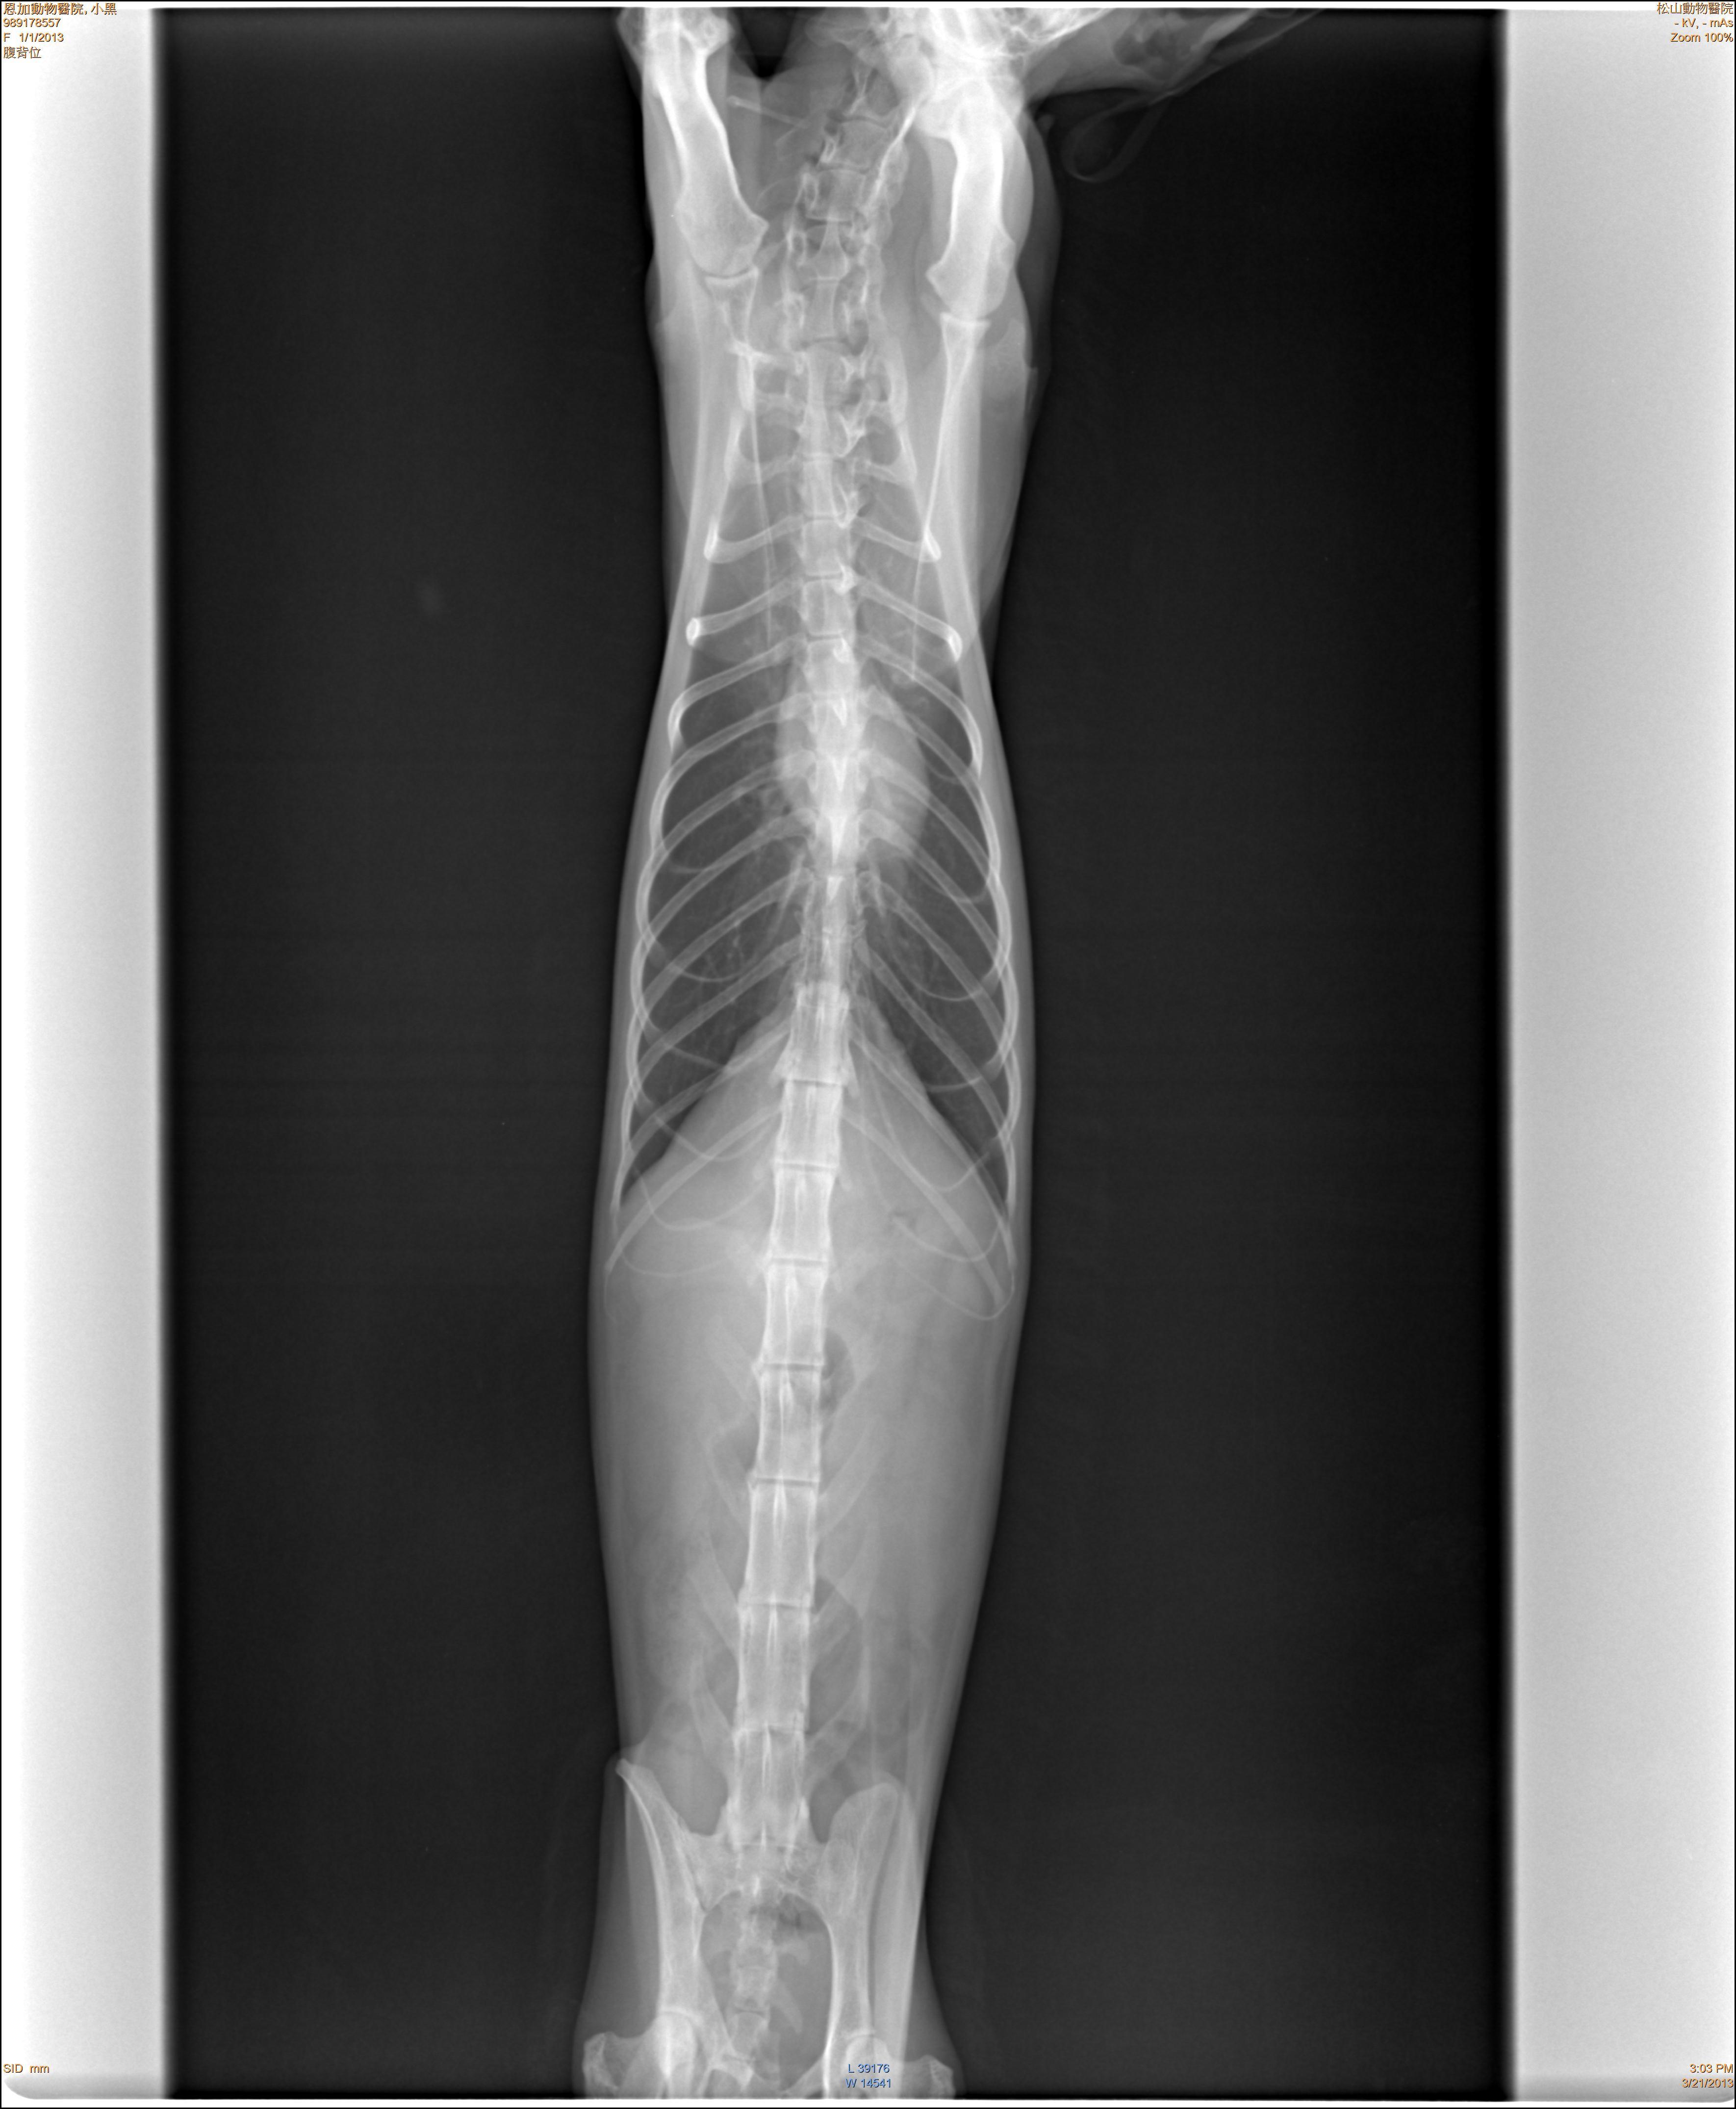

主題: 消瘦不吃虎斑貓 申請者姓名: 張慧敏 花色: 申請日期: 2013-05-08 18:09:34 申請者部落格: 申請者臉書網址: 所在縣市/合作醫院: 台北市/恩加動物醫院 治療費用: 14400元 需求人數: 32人 已結案 (2013-08-06 14:17:12) 報名人員: alicelin x4(已付款)、Amanda Lo x2(已付款)、Linda(已付款)、Chloe Liang(已付款)、Nico Huang(已付款)、treaci(已付款)、林雅雯(已付款)、lavinia x2(已付款)、Ray Lei(已付款)、Emily Chou x10(已付款)、Rebecca Wu(已付款)、Lulu Hsieh(已付款)、假不妙(已付款)、Winnie Chou(已付款)、Antelie(已付款)、Page Chang(已付款)、簡楓峻、簡楓峻、kid x2(已付款)、 候補人員: 動物病情說明: 在新北市平溪區山上餵養的浪貓,發現體型消瘦不吃東西,精神不佳,送醫治療,經過多項血液生化檢查、X光檢查,點滴治療,仍然回天乏術。